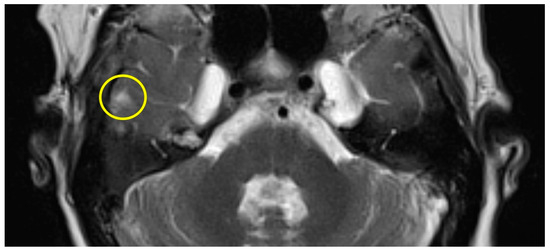

| slight (1) | parts of the inferior temporal gyrus, less than half of the thickness (cranial-caudal) |

| Patient #1 | T2 | f | 58 | left | 12 months | 175 min | slight |

| Patient #2 | T2 | f | 62 | right | 16 months | 159 min | slight |

| Patient #3 | T2 | f | 57 | left | 11 months | 131 min | slight |

| Patient #4 | T1 | f | 49 | left | 12 months | 159 min | slight |